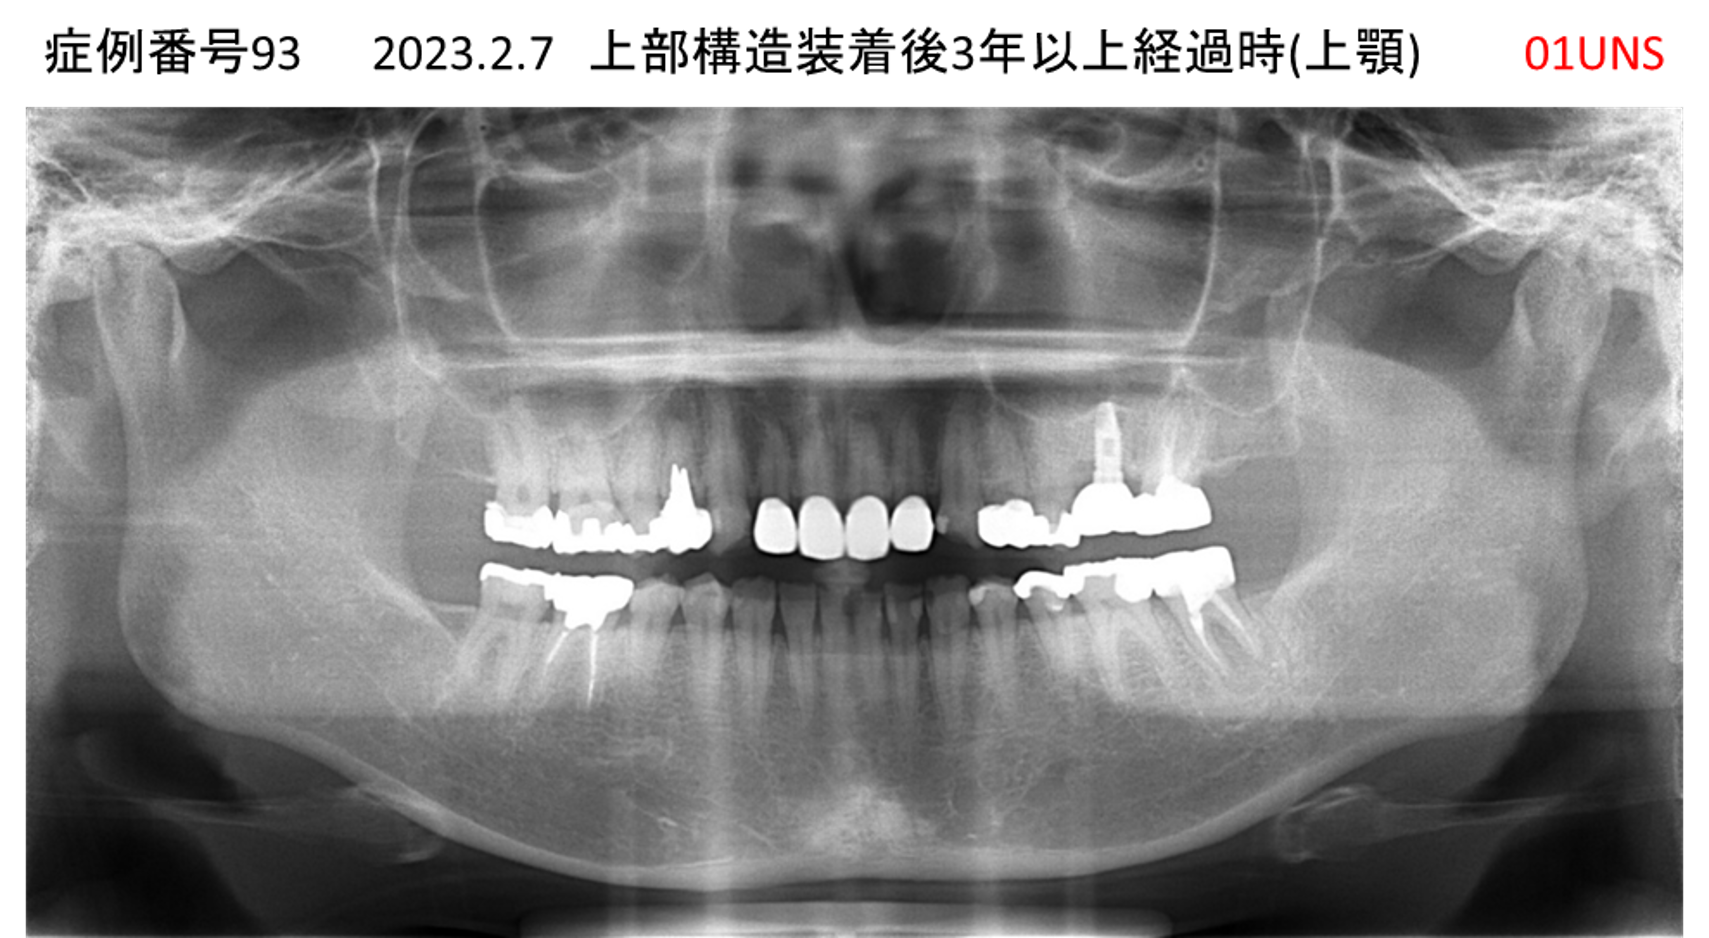

上の前歯が揺れてきた患者様のインプラント症例

| 治療名称 |

インプラント |

| 治療費用 |

390万円+税 |

| 治療期間 |

6か月 |

| 患者さんの症状(主訴) |

上の前歯が揺れてきた。固いものが食べられない。 |

| 治療内容 |

サイナスリフト、抜歯即時インプラント |

| 治療結果 |

上の前歯の揺れが収まった。食べ物がおいしい。 |

| 治療の注意点(リスク/副作用) |

インプラントが壊れたら再治療が必要 |